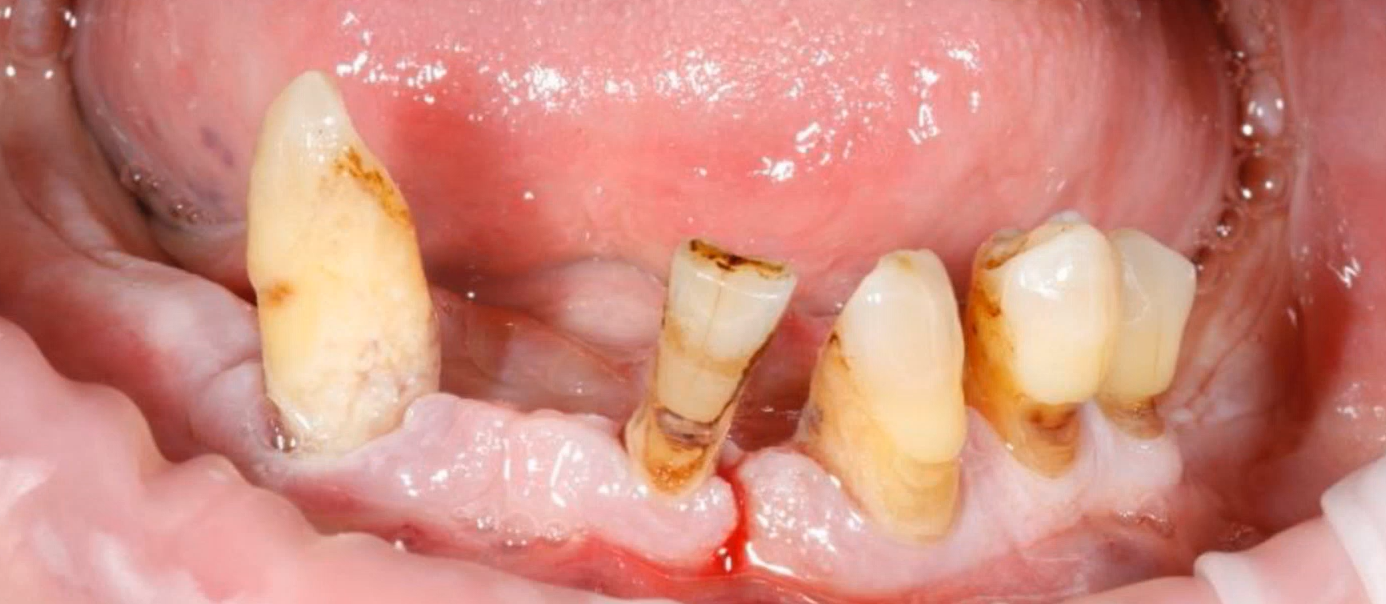

A typical situation in which the remaining teeth are extracted and some implants can be installed in the sockets of recently extracted teeth. YouTube/ Dr. Sergey Rozhnov /sergiodontologist

Just 10–12 years ago, many surgeons discouraged this practice and, in most cases, followed a deferred protocol. As a reminder, this refers to cases where one or more teeth are extracted and an implant is placed immediately afterward. Since the topic of our article is total restorations, we are discussing the removal of all remaining teeth and the placement of the required number of implants. Not all implants will necessarily be placed in the sockets of extracted teeth; the position of the implants is determined by the treatment plan, and several implants may be placed in areas where teeth were lost long ago.

Immediate implantation is now considered a standard procedure, and if there are no contraindications, doctors strive to place the implants immediately. Afterward, two scenarios are possible: